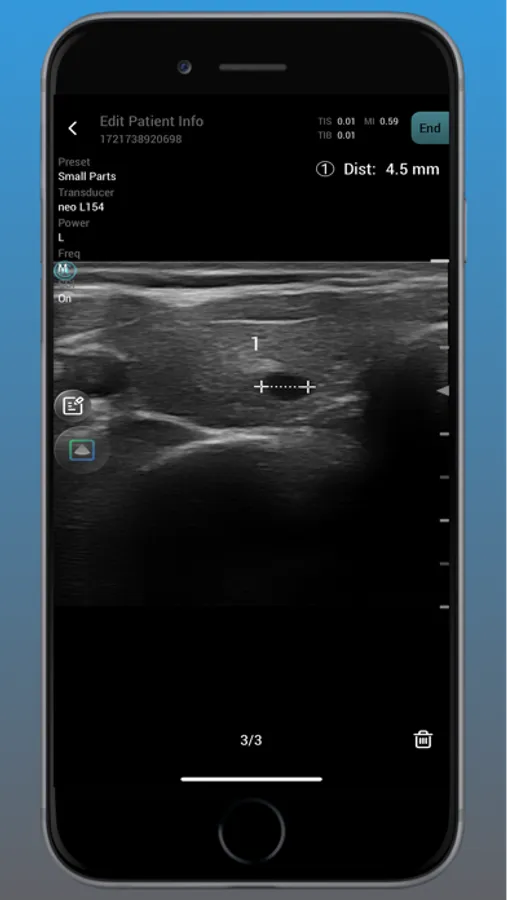

Neo Medical Ultrasound offers high imaging quality in real-time for physicians to improve daily patience care. Neo Medical app features different modes such as B Mode, Color Doppler, Pulsed Wave, and Motion mode. It is designed for medical professionals to easily access user interface to enhance portability and efficiency in daily workflows.

neo Medical Ultrasound System Screenshots